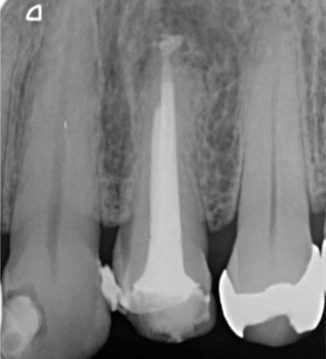

症例3【40代女性】右上74根尖病巣の治療 右上56 洞低膜を挙上しインプラント埋入

治療前

治療後(5年経過)

主訴 右上で物が噛めない。インプラントを希望され来院。

右上第二小臼歯はC₄にて抜歯。右上第一大臼歯は欠損の状態。

残存骨が5~6㎜程で、インプラント埋入には骨の高さが不足している為、ソケットリフト(骨造成)を行った。洞底膜を挙上することで、骨の高さの不足を解消。

採血のよるCGFメンブレンとAFGブロック(人工骨β‐TCPとAFGを混ぜたブロック)を填入しインプラント2本を埋入。約4ヶ月の免荷期間を経て、仮歯を装着、リハビリをし、約5ヶ月後にメタルボンド(金属焼付ポーセレン)を装着。

リスクとしては、ソケットリフト(骨造成)による一過性の副鼻腔炎が起きる可能性がある。まれに洞底膜が破れる可能性がある。ただし、膜は約3週で再生するので、膜の回復を待ち、再オペを行う。

費用 113万(オペ・ソケットリフト・人工骨・採血による濃縮血小板生成・仮歯・最終補綴物まで含む)